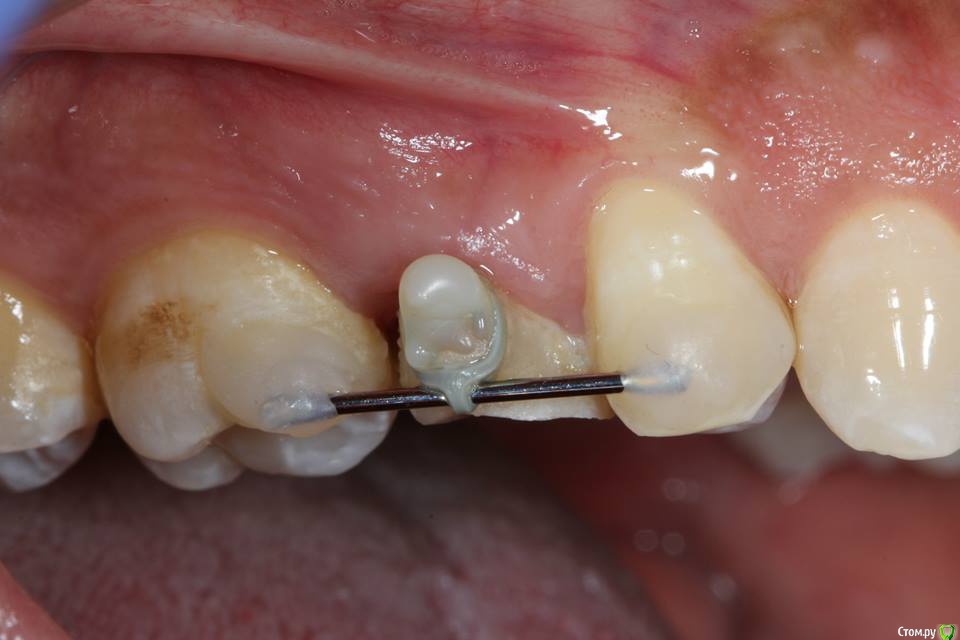

Kolchanov Опубликовано 23 июня, 2015 Поделиться Опубликовано 23 июня, 2015 Экструзия одиночного зуба для получения хоть какого-нибудь феррула. Подозреваю, что процедура не очень сложна и вполне модет быть освоена простым терапевтишкой, т.е. мной. Был бы очень благодарен, если бы кто-нибудь накидал своих мыслей по этому поводу, а еще лучше и фоток. И, конечно же, перечисление материалов. В одной из клиник, где я работаю, делают так иногда.После удаления штифтового зуба имеем поддесневой дефектhttp://s010.radikal.ru/i311/1506/49/4f3a03a5b53b.jpghttp://s010.radikal.ru/i313/1506/55/c752a532f478.jpgПациентка пожелала зуб сохранить. Теперь его тянут. И пятерочку еще в придачу.http://s014.radikal.ru/i327/1506/75/e9897bfb0e24.jpghttp://i024.radikal.ru/1506/99/1f1453b881ef.jpghttp://s017.radikal.ru/i434/1506/ea/caf4284659b4.jpghttp://s018.radikal.ru/i522/1506/ae/b2b54bddcdb8.jpghttp://s015.radikal.ru/i331/1506/7c/0efe752f8c35.jpgПока ничего сложного не вижу.У меня сейчас есть похожий случай. Но, послать в Москву... Не поедут. А на местного ортодонта как-то надежды мало. Я потом залью сюда фотки со своими мыслями. Может кто что присоветует...Спасибо! 1 Ссылка на комментарий

krokomot Опубликовано 25 июня, 2015 Поделиться Опубликовано 25 июня, 2015 (изменено) а вот вам моя идея: через 2 проволочные балки сверху ортодонтическую цепочку за ваши зацепы))http://s017.radikal.ru/i431/1506/b6/5d74d8cbbd5a.jpgплюс конструкциив выравнивании силы оральной и вестибулярной)) Изменено 25 июня, 2015 пользователем krokomot Ссылка на комментарий

Kolchanov Опубликовано 25 июня, 2015 Автор Поделиться Опубликовано 25 июня, 2015 а вот вам моя идея: через 2 проволочные балкиВот! Именно так я и собирался сделать, если ортодонт местный сольется. Только я не знаю что такое цепочка ортодонтическая. Хотел просто тягу эластичную какую-нибудь кинуть. Типа кольца сепарационного. Ссылка на комментарий

Kolchanov Опубликовано 25 июня, 2015 Автор Поделиться Опубликовано 25 июня, 2015 (изменено) Вопрос такой - при ортоэкструзии обязательно нужно каждую неделю "подрезать" круговую связку? По теме есть вот такой кейс, автора к сожалению не помню.Это Григория (ForestDent) кейс. Связку надо обязательно резать, чтобы без кости вытягивался. Изменено 25 июня, 2015 пользователем Kolchanov 1 Ссылка на комментарий